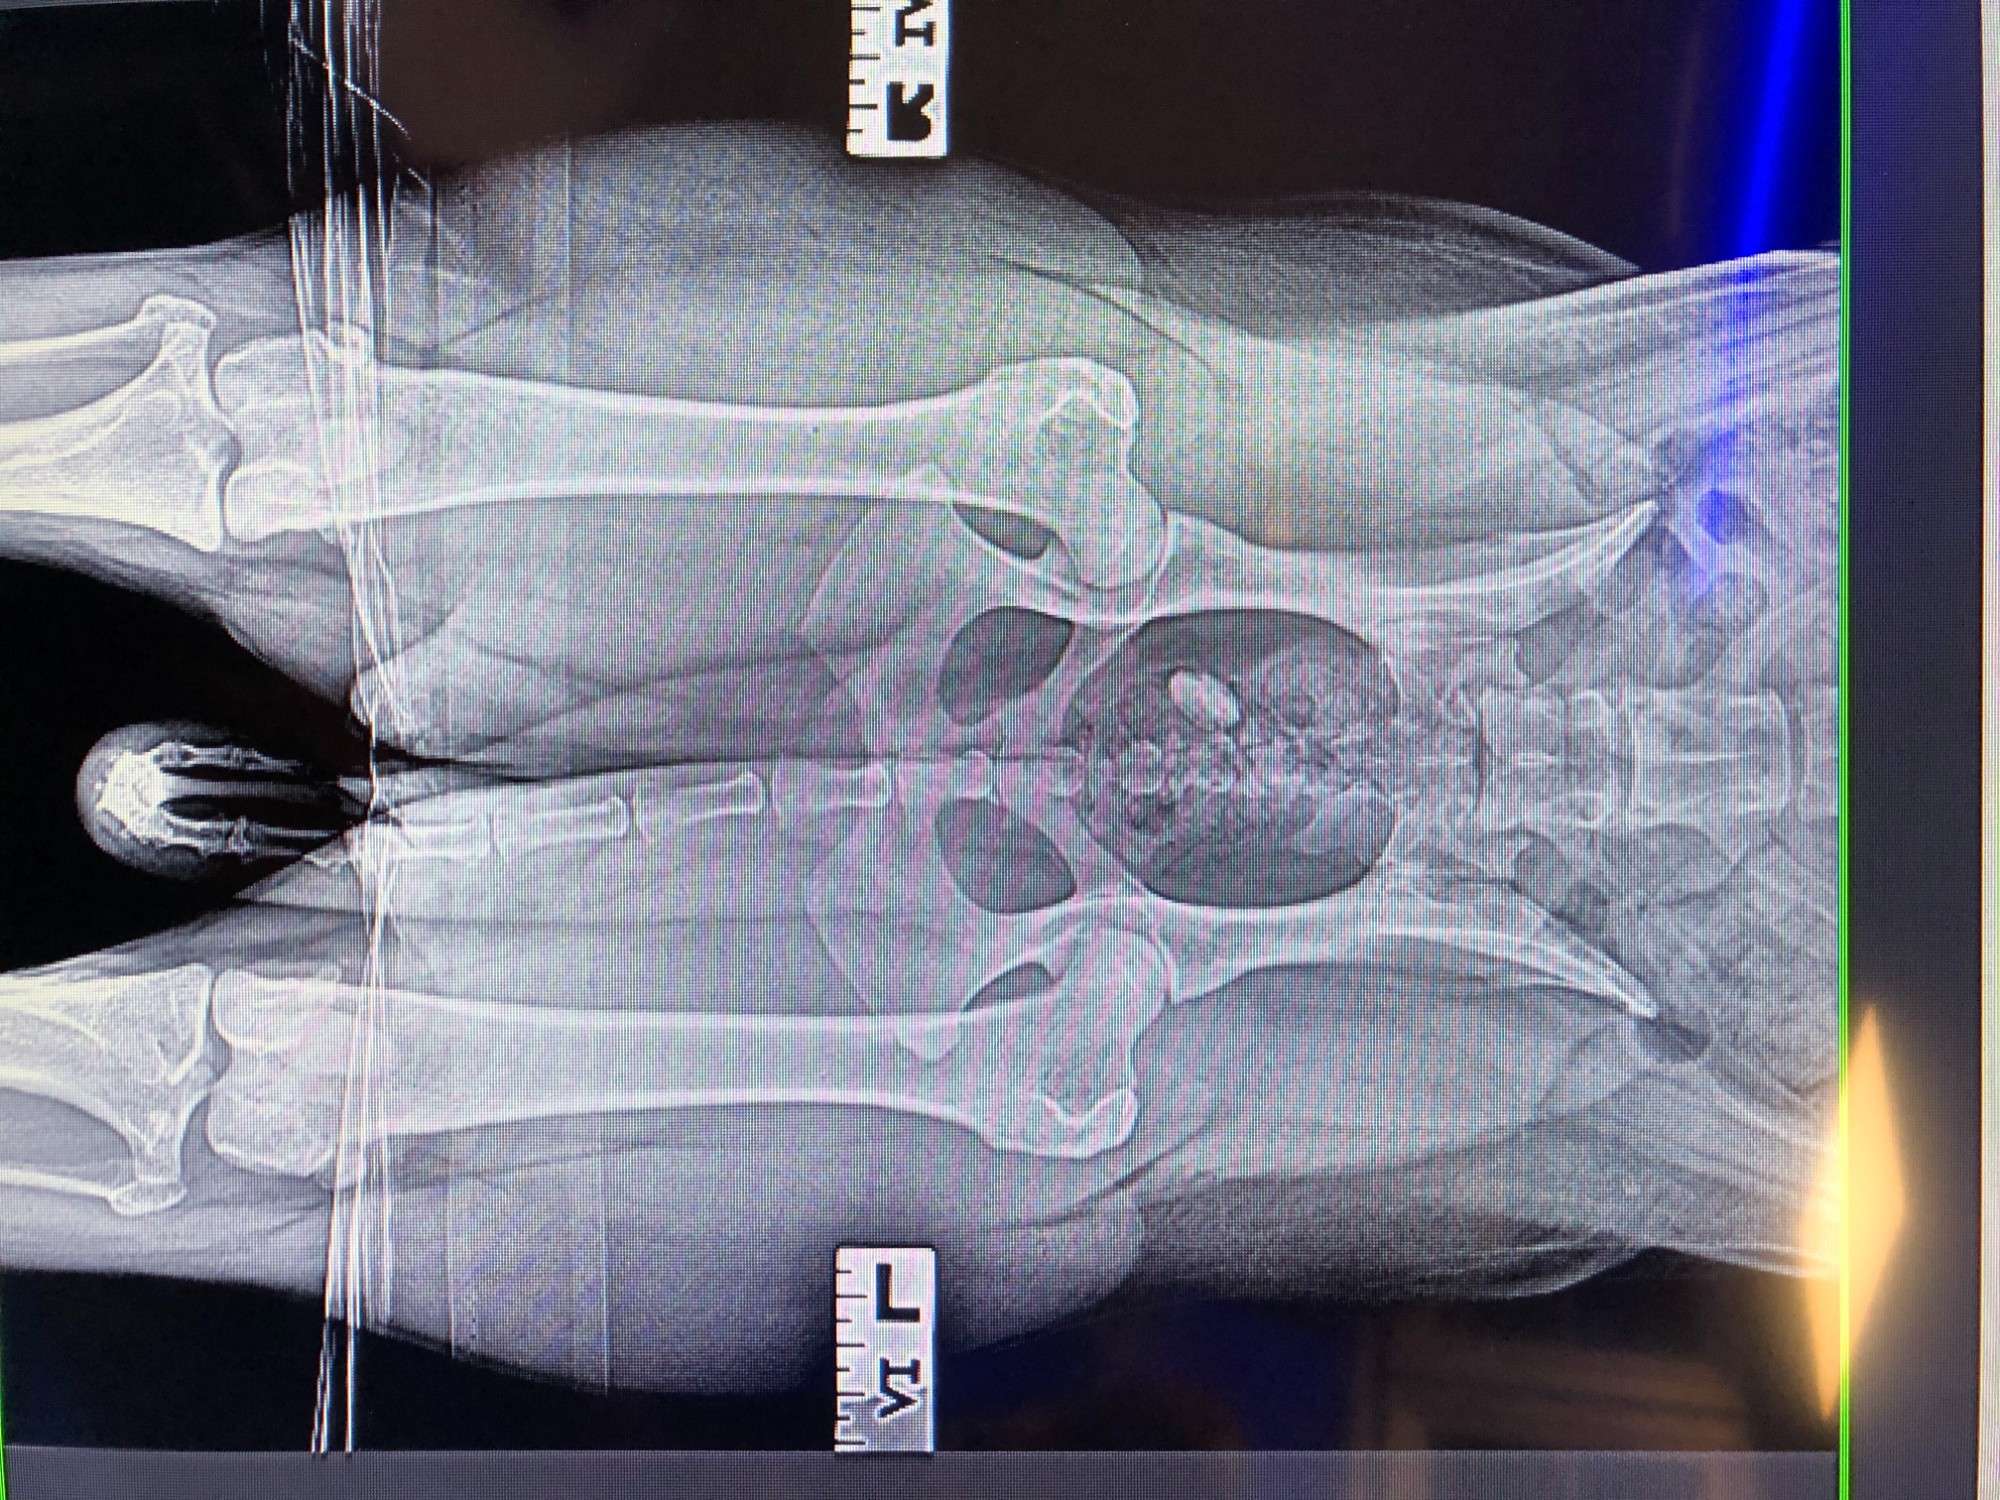

Pipers hip xrays

Pipers CCA